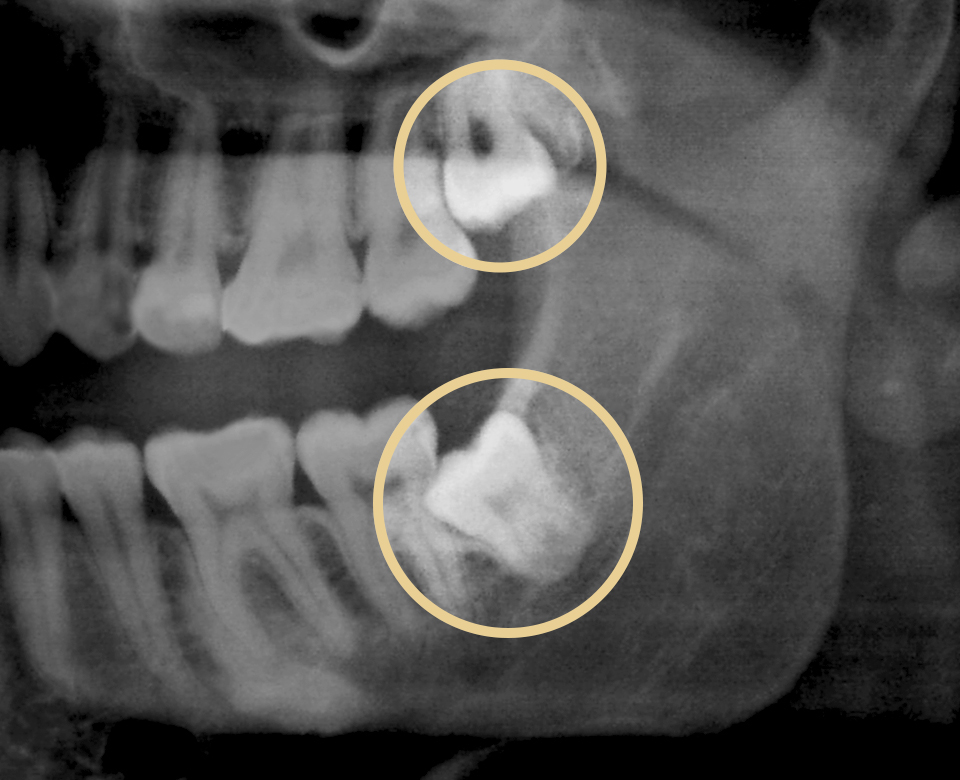

대학병원에서 해야 한다는

어려운 케이스의 사랑니까지

일반 사랑니부터 고도의 집중력과 테크닉을 요구하는

완전 매복 사랑니까지 다양한 케이스의 사랑니를

전문적으로 진료하여 안전한 발치를 진행합니다.

사람에 따라 다르지만 사랑니는 대부분 뼈의 자리가 부족하거나 기울어져 나거나 일부분에만 나오게 되어 관리가 매우 힘들고 인접 치아에 충치까지 유발할 수 있습니다. 매복사랑니는 고난이도 기술이기 때문에 숙련된 의사의 발치가 중요합니다.

남양바른탑치과는 풍부한 경험을 갖춘 의료진이 디지털 장비를 통한 정밀 진단을 통해서 사랑니의 위치, 각도, 깊이, 신경과의 거리 등을 파악하고 알맞은 방법으로 매복사랑니도 안전하게 발치를 진행할 수 있도록 합니다.